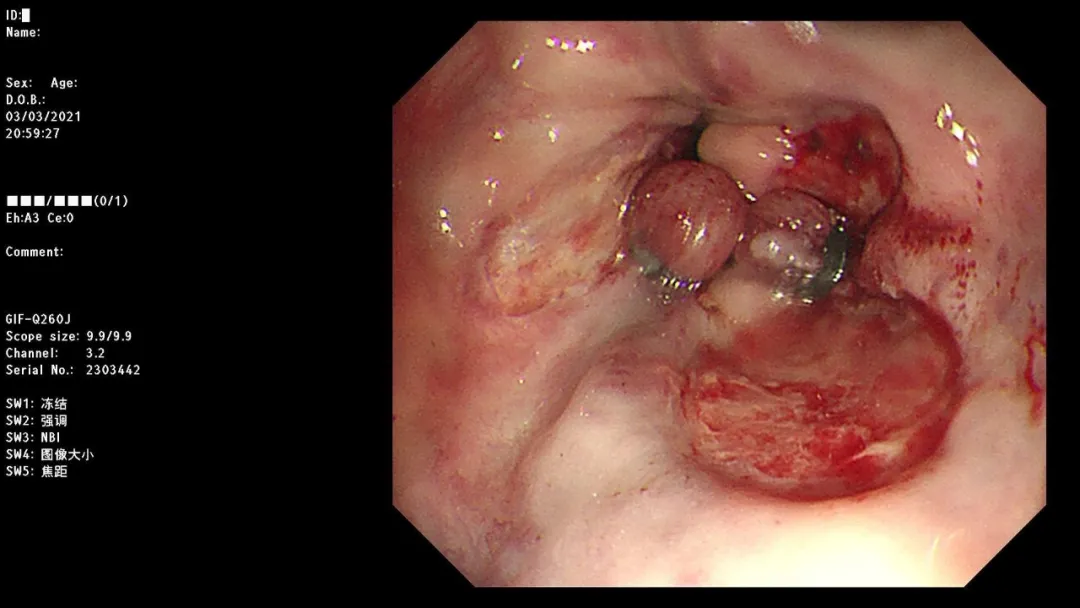

病例一:男,71岁,以“黑便2天,呕血1小时”,于南大一附院消化科就诊,以“上消化道出血”收治住院。

急诊胃镜示:十二指肠降段活动性渗血,予钛夹夹闭,检查诊断:十二指肠降段多发血管畸形并出血急诊钛夹止血术。